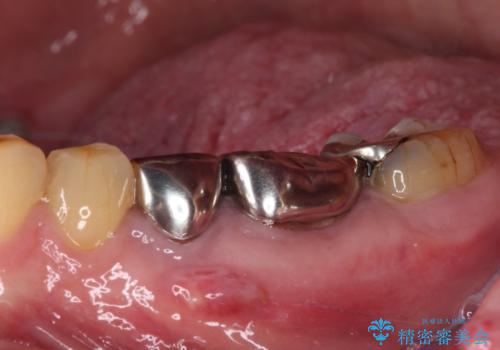

- 上下の奥歯が痛いとのことで来院された患者様です。

診察をしたところ、上下大臼歯の歯肉に排膿路認められたため、根管治療を行い、その後補綴治療を行うこととしました。

また、上顎の欠損部位にはインプラント治療を行うこととしました。

治療を開始したところ、上顎は排膿路が消失し、症状も落ち着きましたが、下顎は一向に改善されませんでした。

改めて診療を行ったところ、歯根破折が認められ、抜歯後にインプラント治療を行うこととしました。